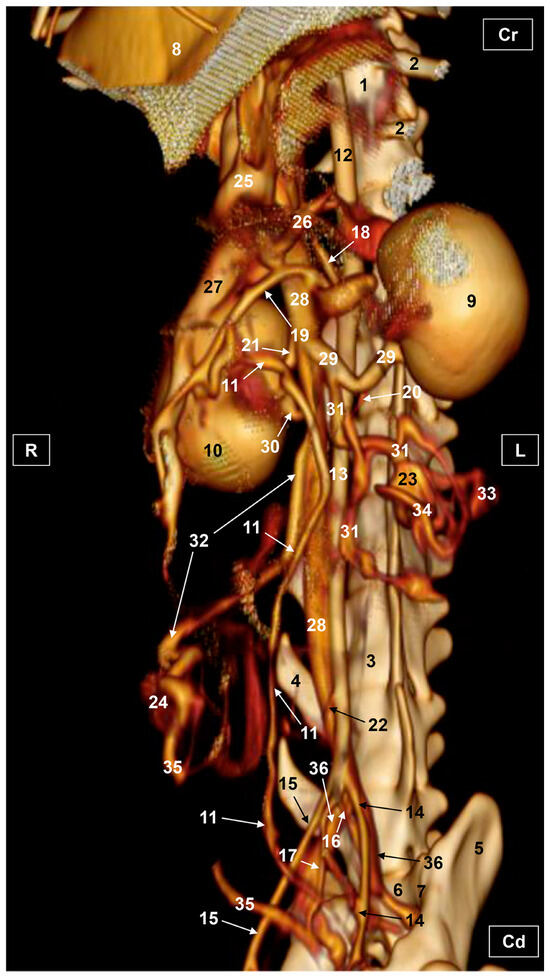

3.2. Computed Tomography Angiography and 3D Printing

3.2.1. Arterial System

3.2.2. Venous System